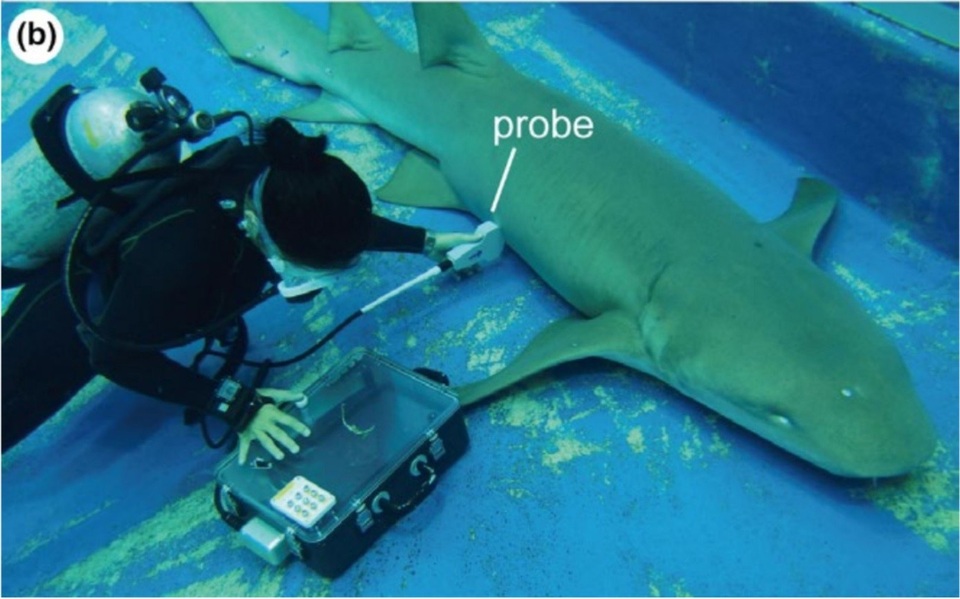

Các nhà khoa học đã sử dụng thiết bị siêu âm dưới nước - công nghệ mới - để nghiên cứu cá mập y tá hung đang mang thai trong điều kiện nuôi nhốt (không giống như nhiều loài cá khác, một số loài cá mập sinh con chứ không phải để trứng).

Siêu âm dưới nước cho cá mập y tá hung mang thai. Ảnh: Ethology.